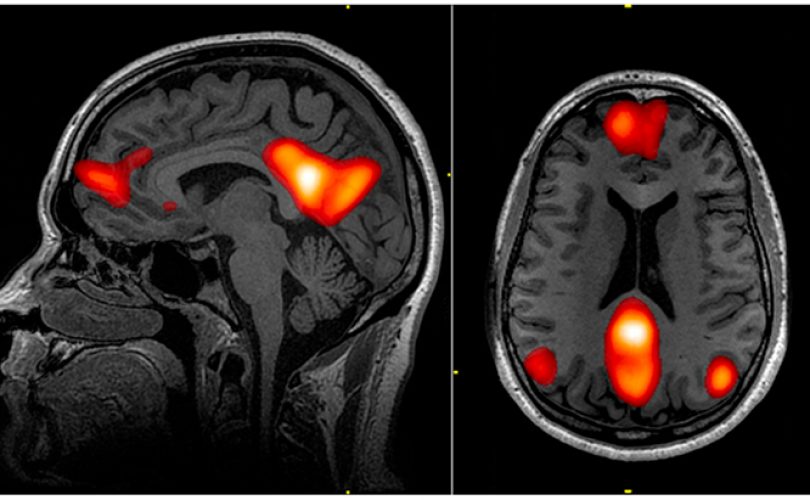

Beyindeki sinirsel iletimin büyük oranda elektriksel bir biçimde sağlanması, keşfedildiği günden bu yana ilgi çekici bir konu oldu. 2000'li yılların başından itibaren bilim insanları "beynin elektriksel yapısına müdahale edilerek beyin hastalıklarının iyileştirilebileceğine" dair düşünceyi sistematik bir biçimde denemeye koyuldular. Beynin elektriksel yapısına müdahale etme yöntemi olarak son döne...

"Mutlu Olma Sanatı" isimli kitabında insanın yaratıcı fikirler ortaya koyması için boş durmaya ve monotonluğa ihtiyacı olduğunu iddia eder. Gerçekten de birçoğumuz hayatımızı değiştiren bazı fikirlerin aklımıza bomboş durduğumuz anlarda geldiğini deneyimlemişizdir. Peki gözümüzü kapatıp dinlenmek için uzandığımızda ya da öylece bomboş uzaklara baktığımızda beynimizin içinde neler oluyor? Uzun yüzy...